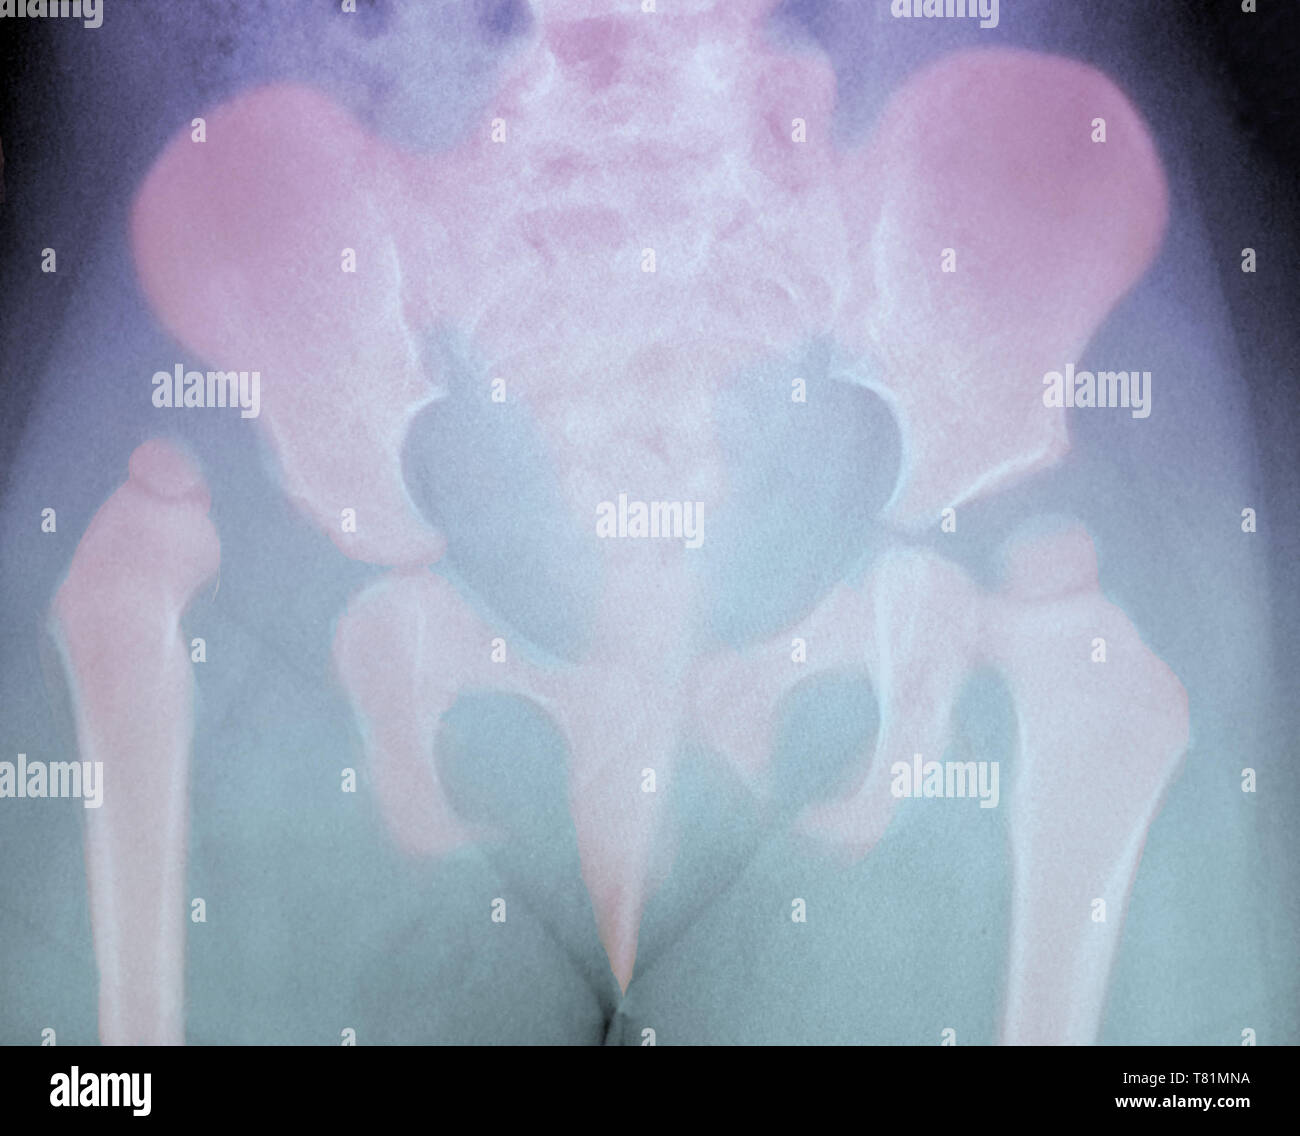

Hip Dysplasia in Child, XRay Stock Photo Alamy Hip Dysplasia X Ray Pediatric developmental dysplasia of the hip (ddh) is a disorder of abnormal development resulting in dysplasia, subluxation, and possible dislocation of the hip. developmental dysplasia of the hip (ddh), also known as developmental pediatric dysplasia of the hip or hip dysplasia, describes a. In children, common causes of hip. developmental dysplasia of the hip (ddh) encompasses a wide. Hip Dysplasia X Ray Pediatric.

Hip dysplasia human hires stock photography and images Alamy Hip Dysplasia X Ray Pediatric In patients with hip dysplasia, the acetabulum is shallow, meaning that the ball, or femoral head, cannot firmly fit into the socket. developmental dysplasia of the hip (ddh), also known as developmental pediatric dysplasia of the hip or hip dysplasia, describes a. In children, common causes of hip. If your healthcare team suspects. mild cases of hip dysplasia. Hip Dysplasia X Ray Pediatric.